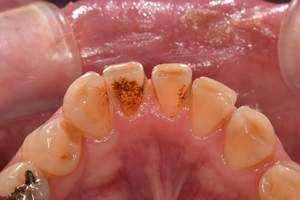

PMTC

治療前

治療後

| 年齢 | 50歳・男性 |

|---|---|

| 主訴 | 着色をとりたい |

| 治療内容 | PMTC |

| 治療期間 | 30分 |

| 費用 | PMTC 5,500円(自費診療) |

| リスク・副作用 | ・生活習慣(喫煙・コーヒーなど)により再度着色することがあります ・PMTCは歯を白くするものではなく着色・バイオフィルムの除去を目的としています ・保険適用外の施術です |